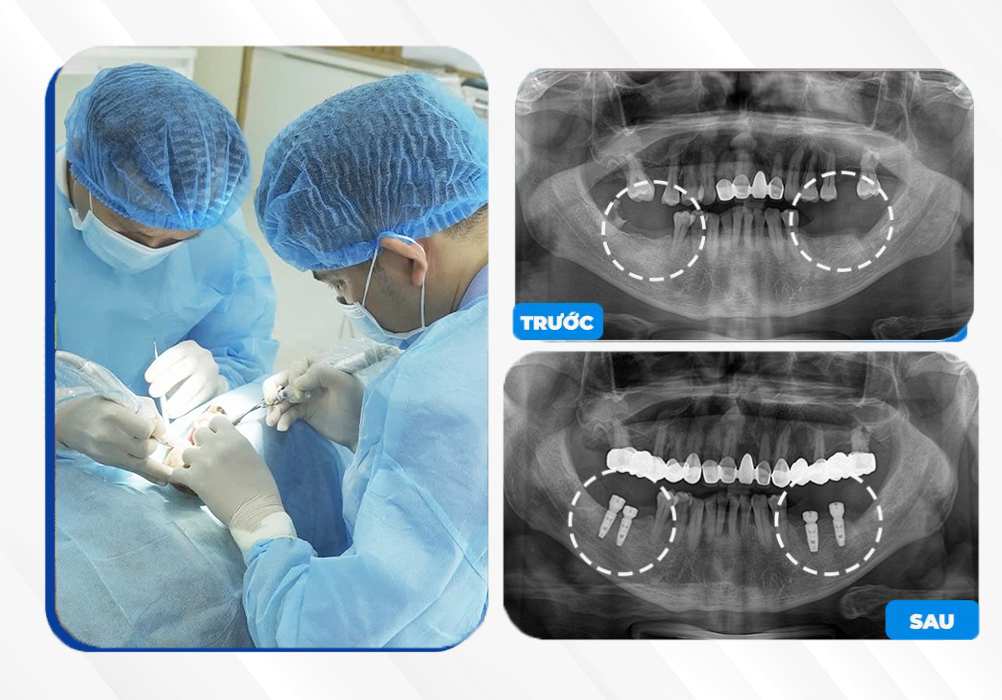

KH. Trần Văn Nam

Cấy ghép 4 trụ Implant

Trồng răng Implant Gia Lai